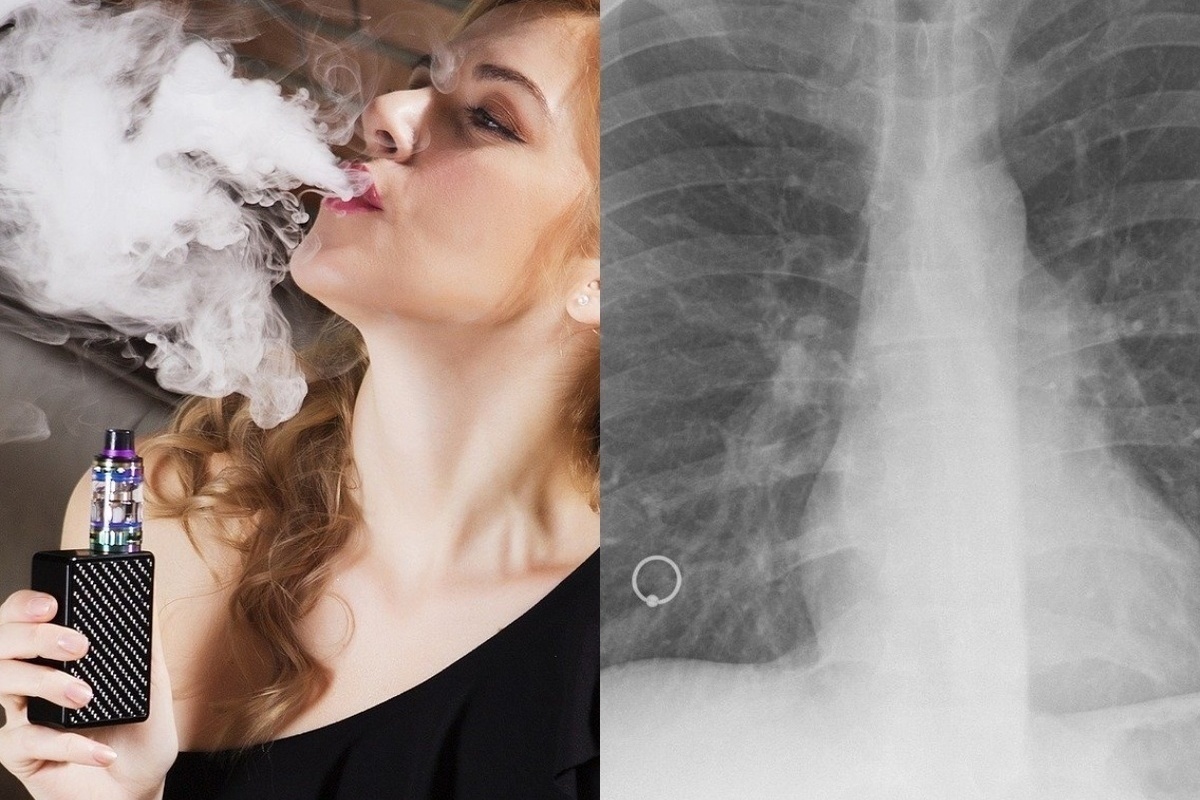

Влияние вейпа на легкие: Фотографии и исследования

Раздел: Визуальный дайджест